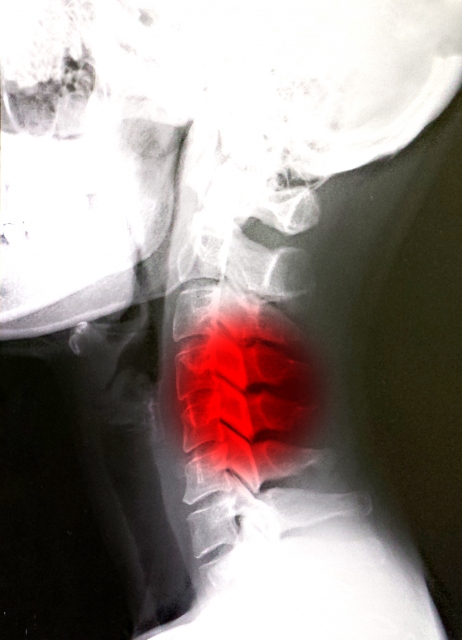

- 頚椎(首の骨)の疾患: 頚椎ヘルニア、変形性頚椎症など